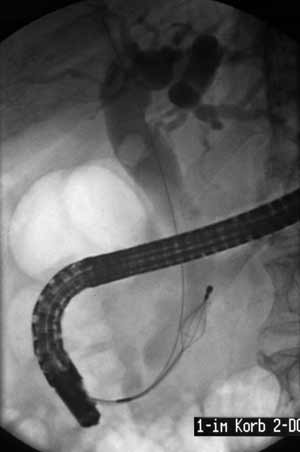

Рис. 4. Расширение холедоха. Камень в холедохе. Литоэкстракция корзинкой Дормиа FG-22Q. Струна-проводник в холедохе.